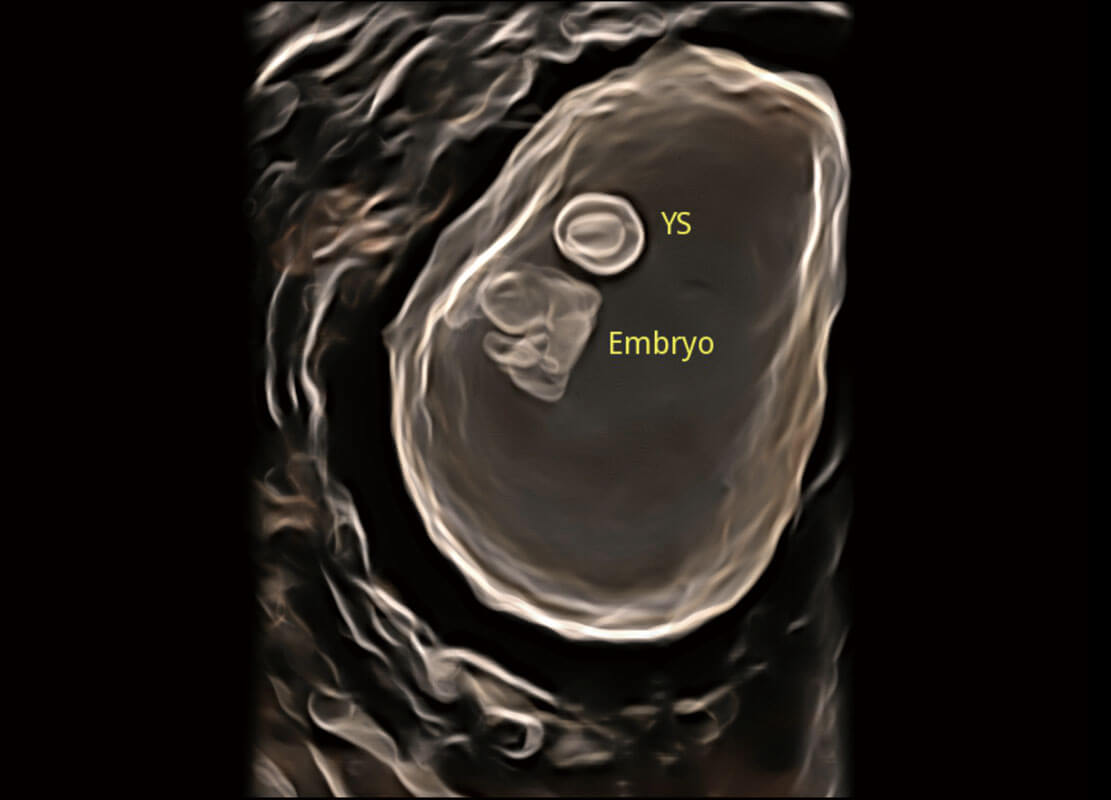

• 高分辨率容积成像-早孕胎儿

• 光影成像-孕囊